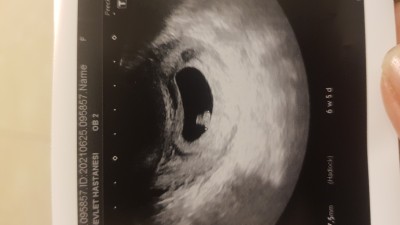

vajinadan alındı görüntü keseden bebegin durusundan cinsiyet tahmini yapabilen var mi acaba cok merak ediyorum?

Fasulye gibiyse erkek derler benimde fasulye seklindeydi oğlum oldu ne kadar doğru bilemem ama

ay sekli erkek diyolar

Yuvarlak kese olunca kiz fasulye gibi olunca erkek diyorlar ama.ne kadar doğru bilmiyorum. Bizde 13+2 haftaligiz kızım olacak inşallah:)

Ilk kizimi hatirlamiyorum ne taraftaydi ama.kesesi yuvarlakti. Bu kızımda da sol tarafta kesesi de yuvarlakti artık tesadüf mü bilmyrm:) ben hep Allahtan hayirli sağlıklı bir kiz evlât istedim  verdi çok şükür. Cinsiyetini ne istiyorsan o şekilde dua et Allaha  Rabbim kabul etmeyeceği duayı ettirmez :)